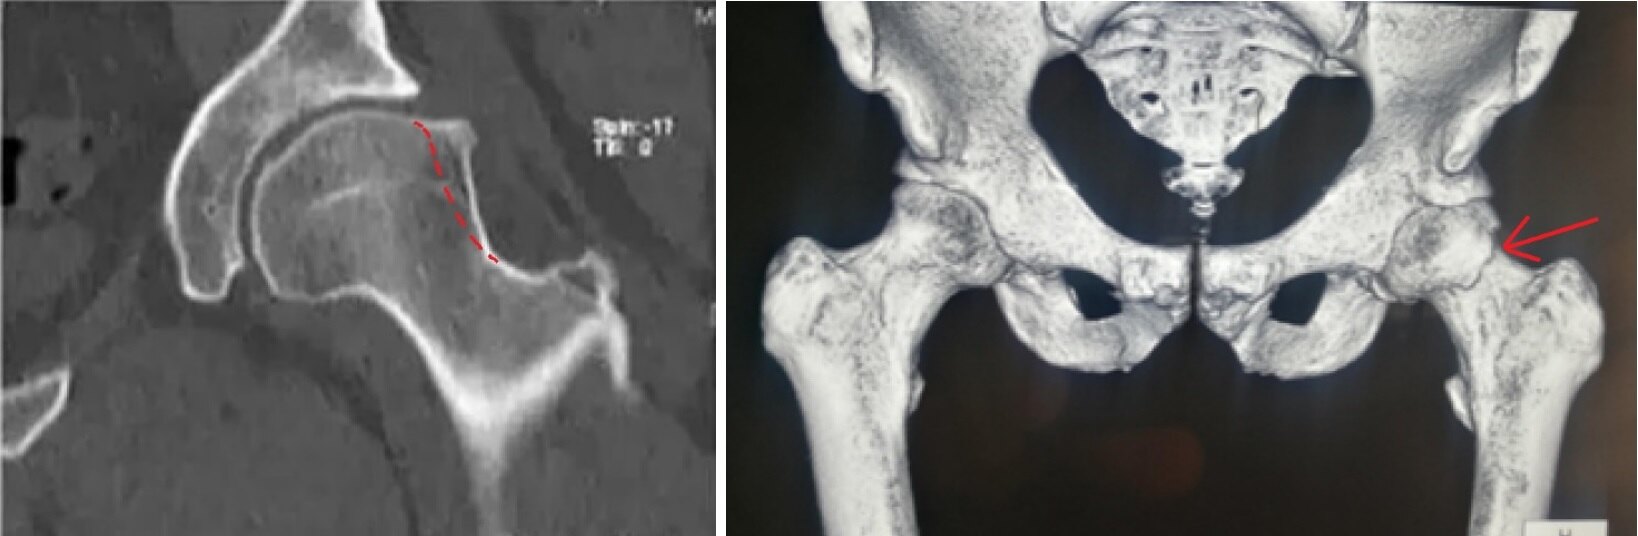

(2)CT:

图14.患髋CT三维重建可评估手术前后凸轮(Cam)和钳夹(Pincer)的程度和改善情况。